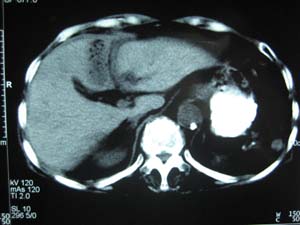

标题: CT15625:女性78Y,十天前胃镜示胃穿孔,现低热 [打印本页]

标题: CT15625:女性78Y,十天前胃镜示胃穿孔,现低热

肝脓肿/膈下脓肿?

膈下脓肿

支持--膈下脓肿

膈下及肝脓肿。

考虑多发性肝脓肿。